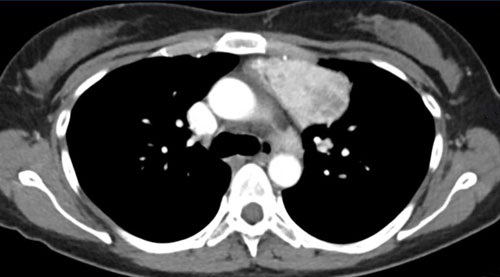

Cardiovascular Pearls on Chest CT...